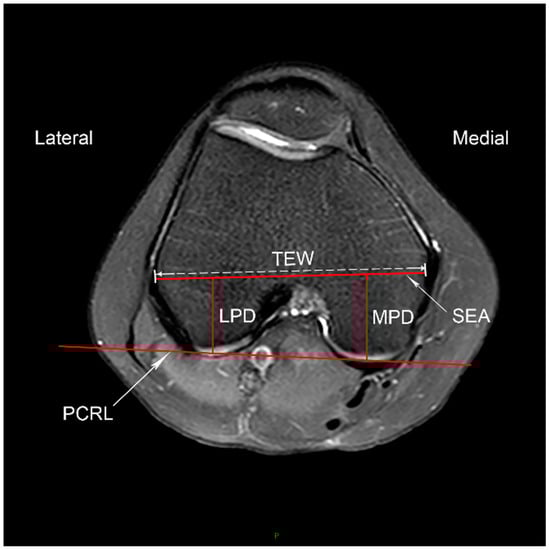

2.3.2. Posterior Femoral Condylar Morphology